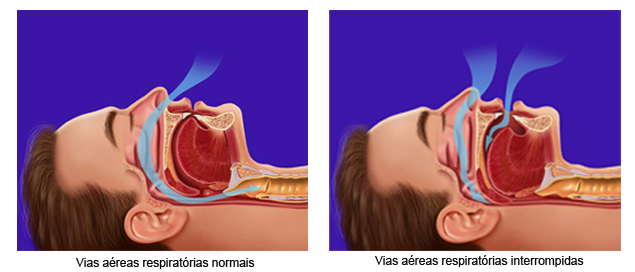

Distúrbio do Sono O ronco é causado principalmente pelo enfraquecimento do tônus muscular da língua e da garganta. O tônus muscular enfraquecido permite a língua relaxar e tombar para trás, tocando a parede posterior da garganta. Quando a língua está muito relaxada ela pode restringir o fluxo de ar normal e vibrar, o que ocasiona o ronco. A maior parte das pessoas que ronca apresenta uma condição conhecida como Apnéia obstrutiva do sono que é caracterizada pela interrupção completa da respiração por um período de 10 ou mais segundos e que ocorre inúmeras vezes durante todo o sono. Pessoas com apnéia do sono obstrutiva, não tem o sono reparador, acordam cansadas, ficam sonolentas durante o dia e podem pegar no sono quando estão dirigindo.

O aparelho usado pela Ortomix funciona avançando a mandíbula e mantendo-a firmemente nessa posição, a grande diferença é que o aparelho indicado pela Ortomix permite movimentos laterais da mandíbula e abertura, o paciente não sente a boca travada. O leve avanço da mandíbula faz com que os tecidos da garganta de “estiquem” aumentando a abertura para a passagem do ar, também o avanço mandibular estimula um reflexo que faz a musculatura da faringe e arredores ficar mais tensa, mais firme, evitando o ronco. Mantendo a mandíbula presa ao aparelho, ele não permite que ela “caia” durante o sono, abrindo a boca, pois esse movimento de abertura geralmente é seguido de um reflexo que faz a língua ir para traz obstruindo a passagem do ar.